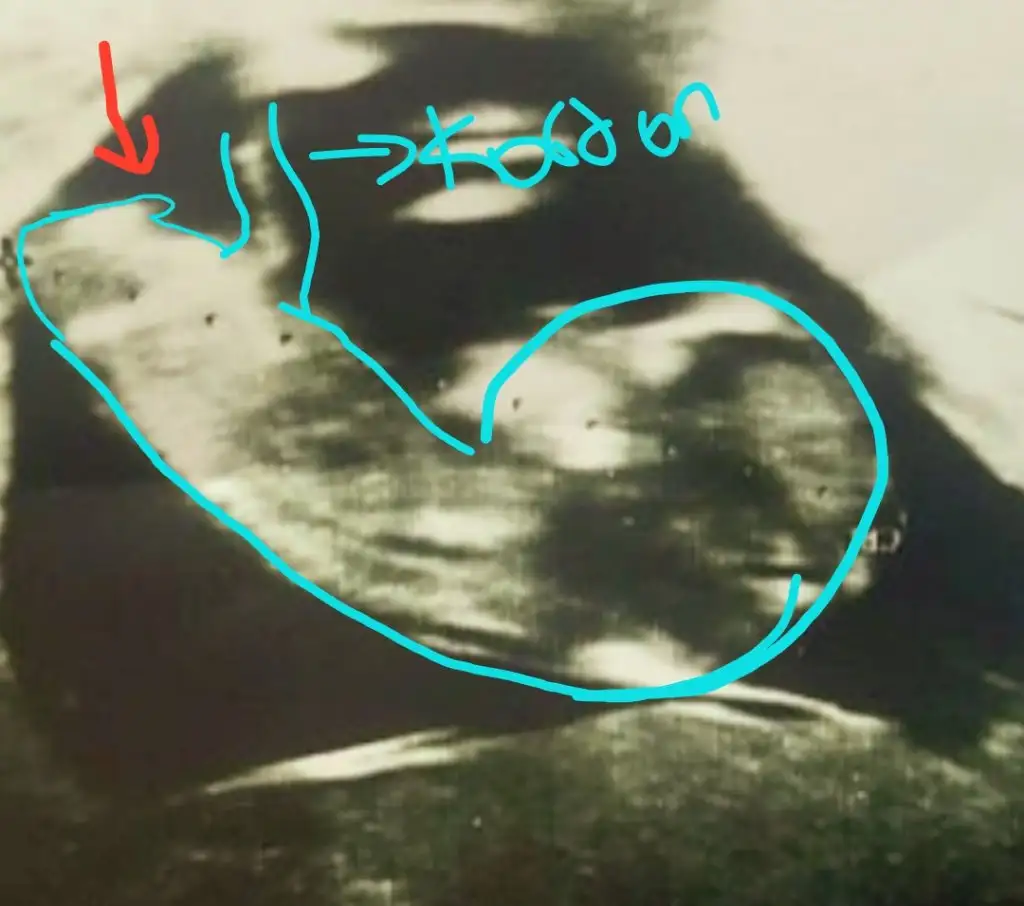

dr soylemeden siz gorun genital nub teorisi ( bebegin cinsiyeti)

Simdi 17 haftaligiz. Bu resimlerdede 12 haftaydi

Önce kıza benzettim demiştiniz 😊 bilemiyorum ama bunu dik görünüyor gibi ❤️ dikkatlice bakarsanız görürsünüz ❤️